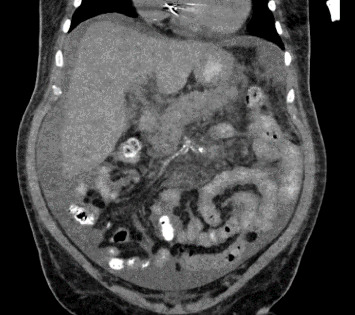

Acute ischemic pancreatitis and duodenitis are uncommon diagnoses that can affect patients with shock. As respiratory, cardiac, and neurological manifestations of shock are prioritized, resultant gastrointestinal (GI) related pathologies can be overlooked, leading to underdiagnosis of these conditions. In this report, we highlight the importance of recognizing acute ischemic pancreatitis and duodenitis in our description of a unique patient presenting with GI related complaints with underlying cardiogenic shock.